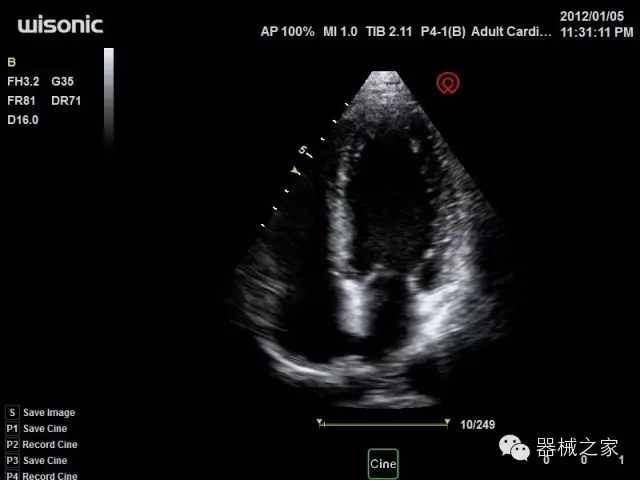

品牌:華聲醫(yī)療(WISONIC)

公司簡介:

深圳華聲醫(yī)療技術有限公司成立于2012年,位于深圳南山西麗湖畔。是一家從事醫(yī)療設備研發(fā)、制造、營銷的新興高新技術企業(yè),目前提供生命信息支持、數(shù)字便攜彩超、移動醫(yī)療服務三個方面的業(yè)務解決方案。公司核心創(chuàng)始人均為醫(yī)療設備行業(yè)領軍人物,在醫(yī)療行業(yè)服務時間平均在10年以上,對行業(yè)和產(chǎn)品積累了深刻的認識。公司在創(chuàng)立之初就有著長遠的戰(zhàn)略目標和規(guī)劃,致力于醫(yī)療設備行業(yè)的細分市場,貼近客戶所需,為大眾的健康提供更多關愛。

官方網(wǎng)站:www.wisonic.cn

經(jīng)典產(chǎn)品:四葉草

臨床圖片賞析

產(chǎn)品特點

·全球目前唯一一款配備主機雙探頭接口,整機重量(含電池)在5公斤以內(nèi)的便攜式彩超;